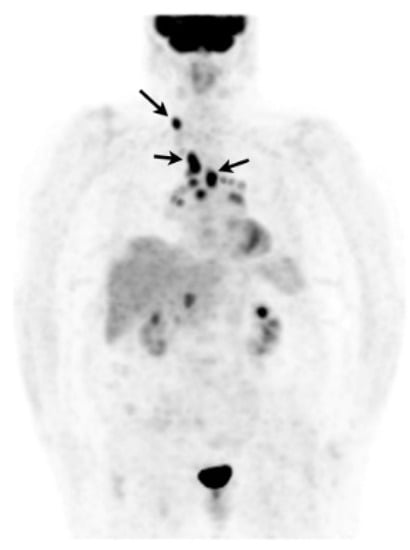

In case of poorly accessible organ localization without superficial nor thoracic manifestation (e.g., cardiac or neurosarcoidosis) 18F-FDG PET may show a suggestive sarcoid-like uptake pattern with hypermetabolic mediastinal and hilar lymph nodes, whether or not combined with lung parenchymal active disease which supports the likelihood of sarcoidosis and orientates a mediastinoscopy [205]. 18F-FDG PET may sometimes reveal smoldering superficial localizations, for example, cervical lymph nodes which are easily accessible to biopsy (Figure 9) [206]. The value of EBUS-guided lymph node sampling in patients with hypermetabolic lymph nodes on 18F-FDG PET remains to be studied.

Figure 9. Caucasian woman (78 years old) suffering from bilateral unexplained panuveitis. Whole body 18F-FDG PET (maximum intensity projection anterior view) demonstrated significant bilateral hilar, mediastinal and right supraclavicular lymph nodes uptakes (black arrows) while there was no node enlargement on chest CT. A subsequent supraclavicular node dissection revealed noncaseating epithelioid granulomas consistent with sarcoidosis. Special staining and culture for mycobacteria were negative.